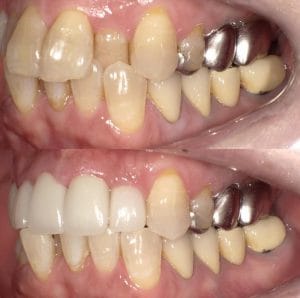

Case016

前歯の審美歯科から、奥歯の虫歯診療、歯がないところのインプラント治療まで口腔内を全体的に当院で治療させて頂いた患者様です。

外見もとても綺麗になり、奥歯でも物を噛めるようになってとても喜んで頂けました。

担当 理事長 佐藤悠野

Case015

前医の被せ物のやりかえを希望された患者様の症例です。

色と形が悪く、汚く見えてしまうという主訴でご来院。

「可能な限り費用を抑えながら、口元が綺麗に明るく見えるようにしたい」というご希望だったので、通常は左右対称の本数で治すことが多いのですが、今回は左上の1番目から右側の4番目までの5本の治療としました。

その場合、一番気をつけなければならないのは色の選択です。

色を左の歯よりも明るくしすぎてしまうと、左右非対称に見えてしまうため、明るくしすぎることはできないし、せっかく治療をするのに綺麗に見えない色を選択するのももったいないです。

同じ白色でも「透明感のある白」と「マットな白」では色の浮き方が全く違います

当院では、白さを追求しながらも透明感のある高品質なセラミックを使用しているため、自分の歯より白いものを使用しても、色が浮かずに全体的に明るく見えるようになっていると思います。

治療回数3回(初回カウンセリング含む)